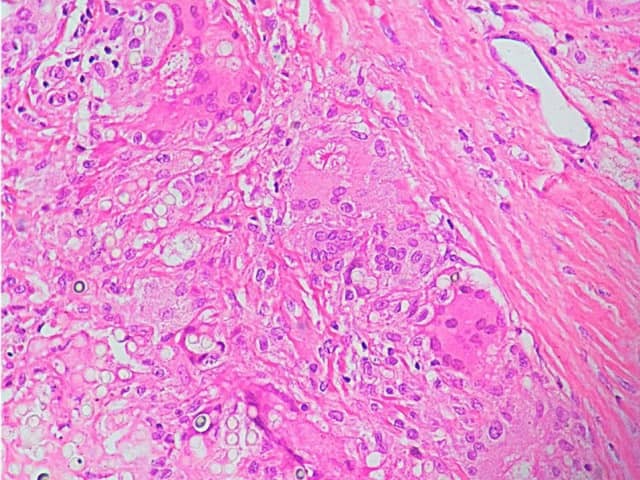

Granulomatous inflammation with giant cells and asteroid body due to lobomycosis